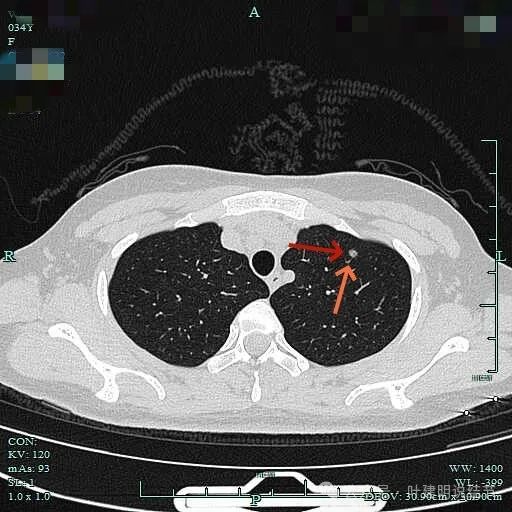

2、影像展示与分析:

病灶内局部似有小空泡或局灶细支气管扩张,有血管贴边进入,整体轮廓与边界较清。

边缘区小血管似乎有拐了个弯,是不是病灶的影响导致的?